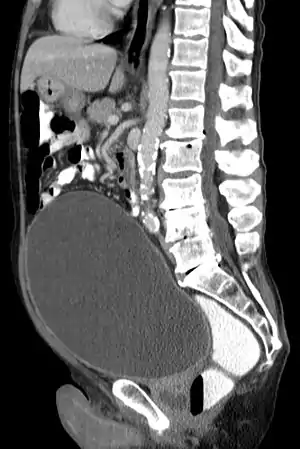

| احتباس ادراری و بزرگی نمایان مثانه در سیتیاسکن. | |